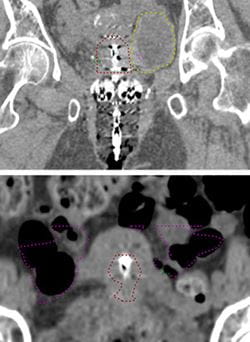

Brachytherapy has been traditionally prescribed to point A (top, indicated in green), a standard point 2 cm above and to the side of the ovoids. Prescribing to Point A can overestimate tumor size. For example, Point A is located in the bladder (top, yellow dotted line) and small bowel (bottom, purple dotted line) in these images. The red dotted line is the target volume.

Traditionally, brachytherapy plans were prescribed to standard points, but doing so could underestimate or overestimate the tumor size (Image above). Instead, image-guided brachytherapy prescribes the dose to the actual tumor volume seen on imaging.